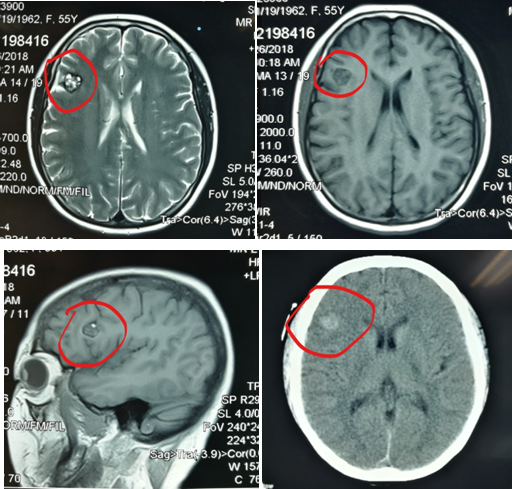

近日,我院收治一病友,因头痛检查发现右额叶运动区旁一大小约1cm病变,考虑海绵状血管瘤。

组图:头颅MRICT发现中央前回前脑实质内占位病变,考虑海绵状血管瘤

完善准备后,通过三维立体定位,找到了病变位置及其与脑沟的关系。术中发现,因患者在患病过程中病变部位曾反复出血,胶质增生及黄染,脑沟深处可见明显病灶区域(定位分毫不差)。术中显微镜下分离脑沟及血管,周围组织无损伤,精准切除病变。病人无任何功能缺失,康复出院。

组图:较小骨窗开颅切除病变。